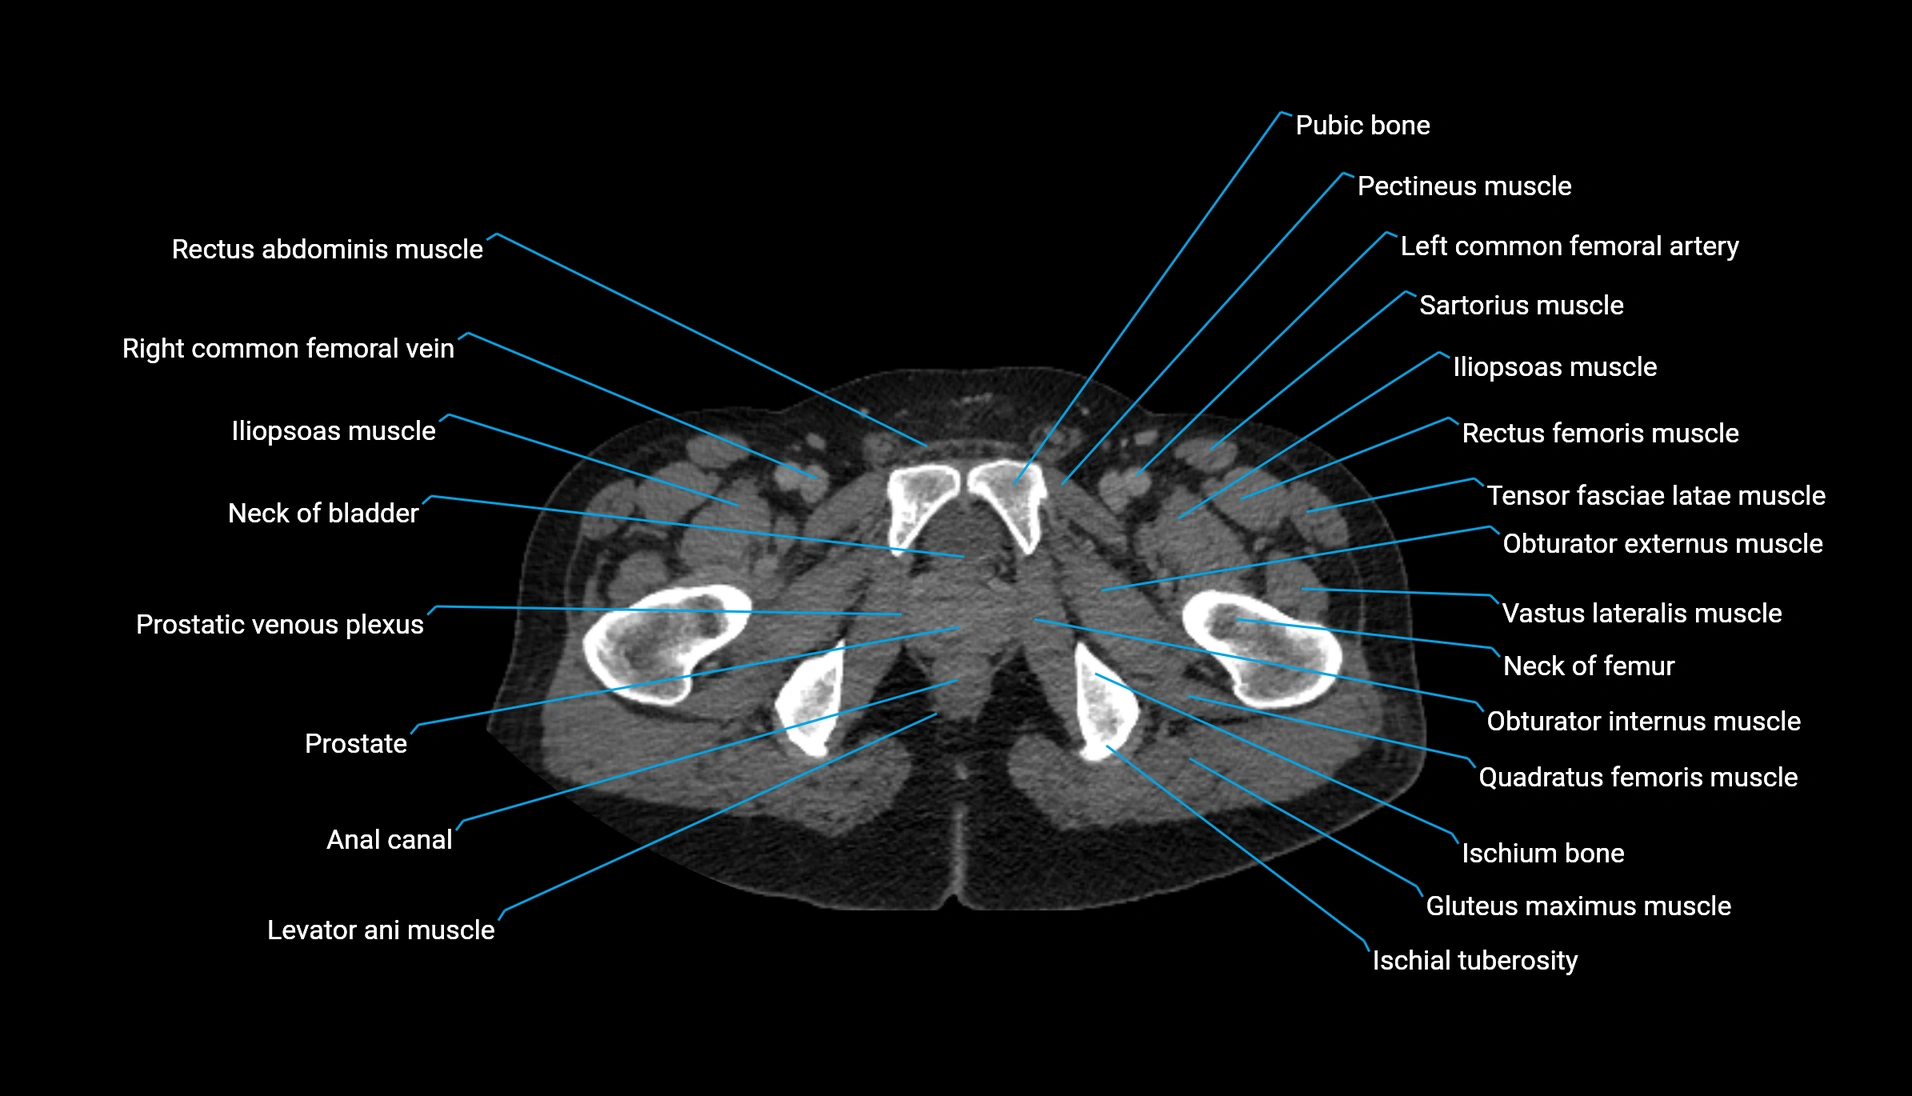

CT Appearance

Non-contrast CT:

-

Demonstrates cortical bone of acetabular rim in excellent detail

Detects fractures, dysplasia, retroversion, or bony overcoverage (pincer impingement)

3D reconstructions used in preoperative hip surgery planning

CT VRT 3D image

CT image